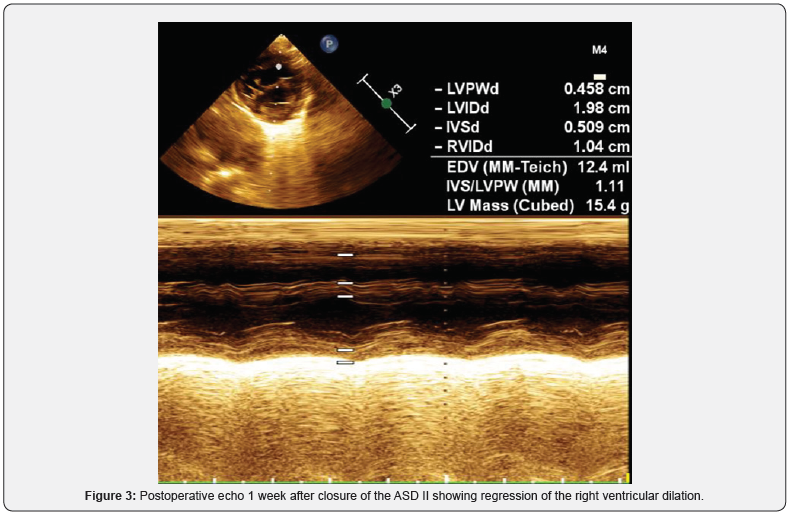

The baby was re-operated 2 days after the cardiac catheterisation (at the age of 3.5 months) and the atrial septal defect was closed with a 3 mm fenestrated pericardial patch. The early postoperative period was uneventful, the clinical condition of the child improved every other day, with marked reduction of the heart failure symptoms. The postoperative echo showed regression of the right ventricular dilation and of the left ventricular hypertrophy and normalization of the left ventricular diastolic function (Figure 3).